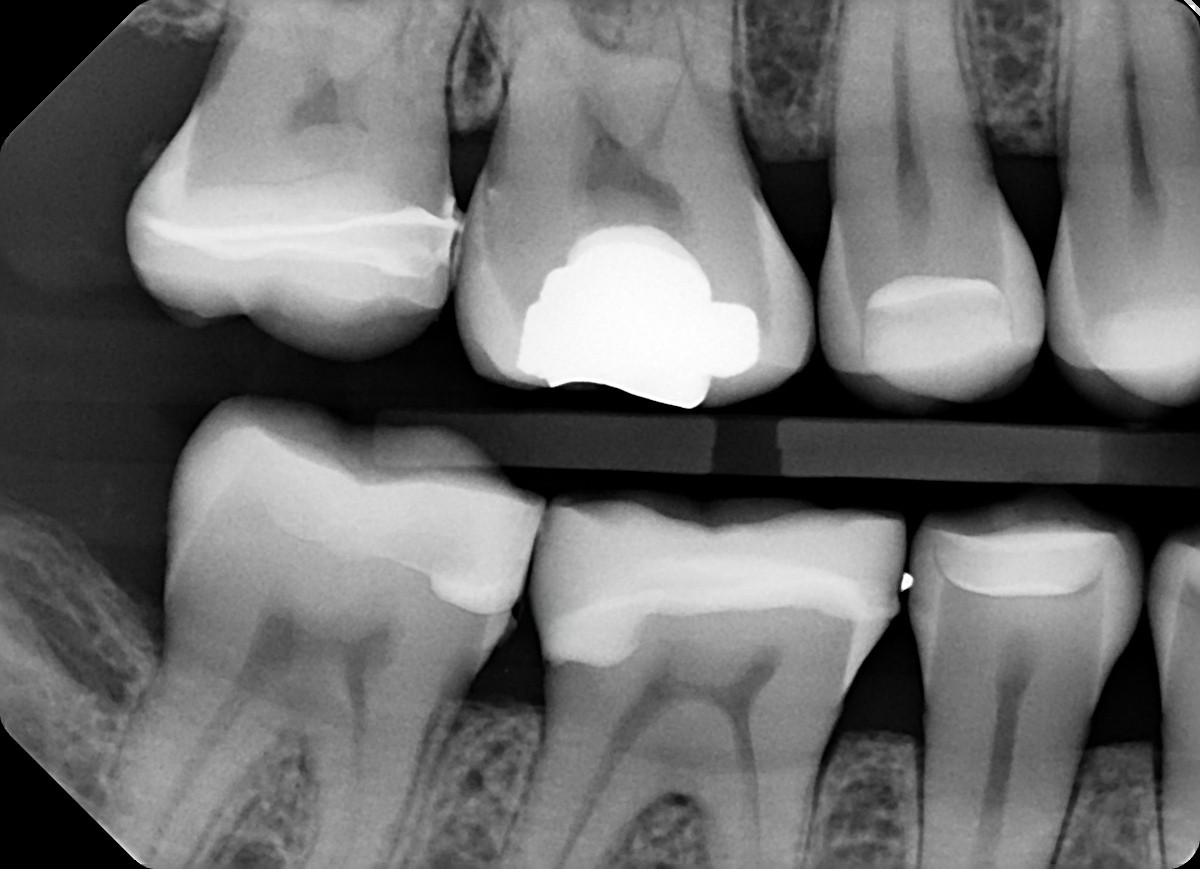

4. In the X ray bellow for which jaw periodontal bone loss is evident?